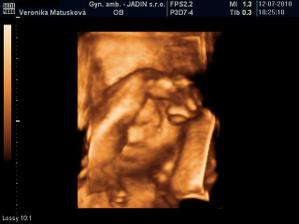

Adamko - 3D/4D

No tot vidno, že je náš syn, sa hanbil a hanbil až sa ukazovať nechcel....ale niekedy sa to podarilo, aj ked to nie je nejaká sláva. Pán doktor nám potvrdil chlapčeka, tak sme radi, vajká ukazoval ako len vedel len toho pipíka stále schovával. Ale je to za nami, pán doktor nás pekne popísal čo je kde, poodmeral nás a povedal, že je všetko v poriadku.